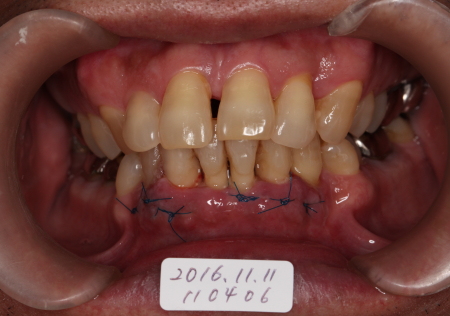

縫合

2016-11-11